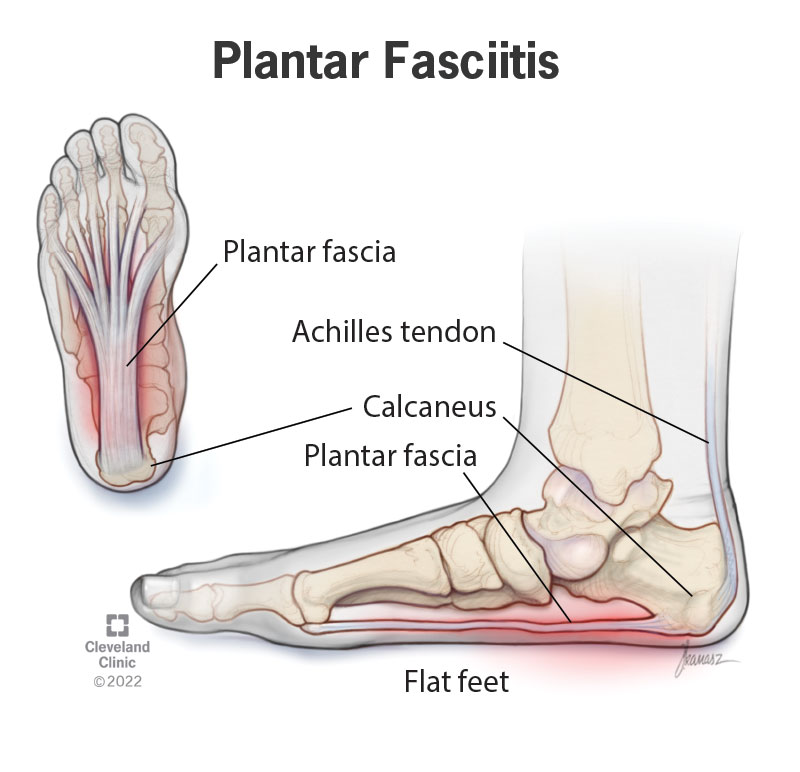

Plantar fasciitis and achilles pain clearance

Plantar fasciitis and achilles pain clearance, Is My Heel Pain Achilles Tendonitis vs Plantar Fasciitis Ease Achilles Heel Pain With These Tips clearance

Plantar fasciitis and achilles pain clearance

Achilles Tendonitis vs. Plantar Fasciitis Which Do I Have Arlington Mansfield Foot Ankle Centers Podiatrists clearance, plantar fasciitis clearance, Heel Pain Causes and Treatment clearance, Achilles Tendon Pain and Plantar Fasciitis Treatment Guide clearance, This Stretch Relieves Plantar Fasciitis Shin Splints Achilles Pain and Heel Pain Focusphysiotherapy clearance, Heel Pain Plantar Fasciitis Delaware Foot and Ankle Group Podiatrist in Newark DE clearance, Plantar Fasciitis and Achilles Tendonopathy InterX Pain Clinic Stratford Upon Avon clearance, Heel Pain Podiatrist Temple Hill Clinton MD Burton J. Katzen DPM clearance, Back of Achilles Tendon Heel Pain Shoes Orthotics Home Treatment clearance, Seattle Bellevue Heel Pain Center Issaquah Foot Ankle Specialists clearance, Interwoven Threads The Plantar Fascia Achilles Tendon Connection clearance, Plantar fasciitis VS Achilles tendinitis Managing Heel Pain Greg Robinson Ibraheem Podiatry clearance, Can Plantar Fasciitis Cause Calf Pain clearance, Plantar fasciitis achilles tendon deals pain clearance, On the morphological relations of the Achilles tendon and plantar fascia via the calcaneus a cadaveric study Scientific Reports clearance, This One Stretch Helps Relieve Plantar Fasciitis Shin Splints Achilles Pain and Heel Pain clearance, Plantar Fasciitis Symptoms and Treatment Doctor clearance, Effective Treatment for Heel Pain Foot Foundation clearance, Plantar Fasciitis Chiropractors in Newmarket ON clearance, Plantar Fasciitis FAQ s clearance, Plantar Fasciitis Symptoms Causes Treatment Options clearance, Is My Heel Pain Achilles Tendonitis vs Plantar Fasciitis Ease Achilles Heel Pain With These Tips clearance, Plantar fasciitis Information Mount Sinai New York clearance, Achilles Tendonitis Plantar Fasciitis clearance, Common Problems that Can Lead to Plantar Fasciitis and Achilles Tendonitis clearance, Heel Pain clearance, Is Plantar Fasciitis Your Achilles Heel Prosper clearance, Plantar Fasciitis Dr7 Physiotherapy Podiatry Hydrotherapy Massage clearance, Foot or Heel Pain It Might Be Plantar Fasciitis Healthy You clearance, Achilles Tendonitis and Plantar Fasciitis Premier Podiatry Velimir Petkov DPM Podiatrists clearance, Achilles Tendonitis Vs Plantar Fasciitis Which Do I Have clearance, Difference between Plantar Fasciitis and Achilles Tendonitis Achieve clearance, Achilles Tendonitis vs. Plantar Fasciitis clearance, Achilles tendonitis vs. plantar fasciitis How to tell the difference clearance, Achilles tendonitis vs. plantar fasciitis How to tell the difference clearance, Product Info: Plantar fasciitis and achilles pain clearance.

Plantar fasciitis and achilles pain clearance

Plantar Fasciitis Symptoms and Treatment Doctor- plantar fasciitis and achilles pain